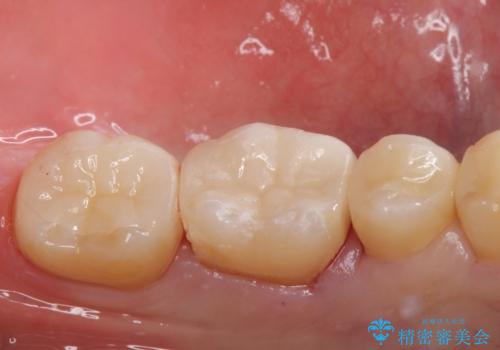

- メンテナンスの患者様です。歯間ブラシをすると染みるとの事で精査したところ歯と歯の間に虫歯が見られました。

拡大鏡下で虫歯を取り除きe-maxインレー治療を行いました。

適合の良い詰め物が入りました。